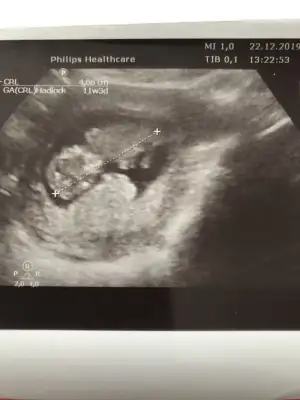

Slm güzel anneler bizde 11+1haftalik olduk bizede bir tahmin edermisiniz

Net degil gördüğüm diklik nub ise erkek gibi ama eminde değilim başka usg varmı 11 yada 12 hafta